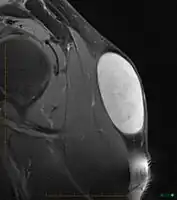

Diagnosis

In terms of the diagnosis of a sebaceous cyst an MRI (Magnetic resonance image) may be used